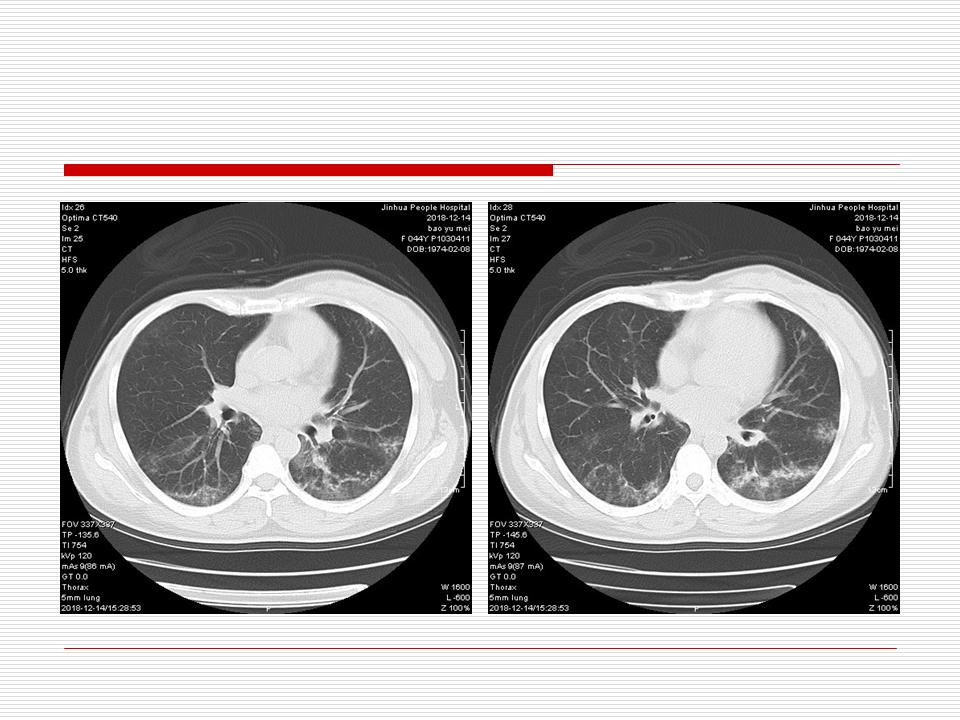

肺部阴影永恒且最重需要鉴别的是:到底是炎症还是肿瘤?但临床的病例中的影像表现难以界定或有些肿瘤特征,同时又有些炎症特点是非常常见的情况。作为临床医生我们怎么去总结分析,并找到之所以是炎症或之所以是肿瘤的细微差别或特点非常重要,也非常有用。2019.12.7浙江省2019年胸心外科学学术年会在宁波召开时,我的临床病例分析与经验总结<那些像肺癌的炎症与像炎症的肺癌>获得在大会交流的机会,以下为该PPT的内容,与你分享,希望对同道有益,有借鉴与启迪。若有探讨与进一不完善的建议,欢迎文末留言讨论: